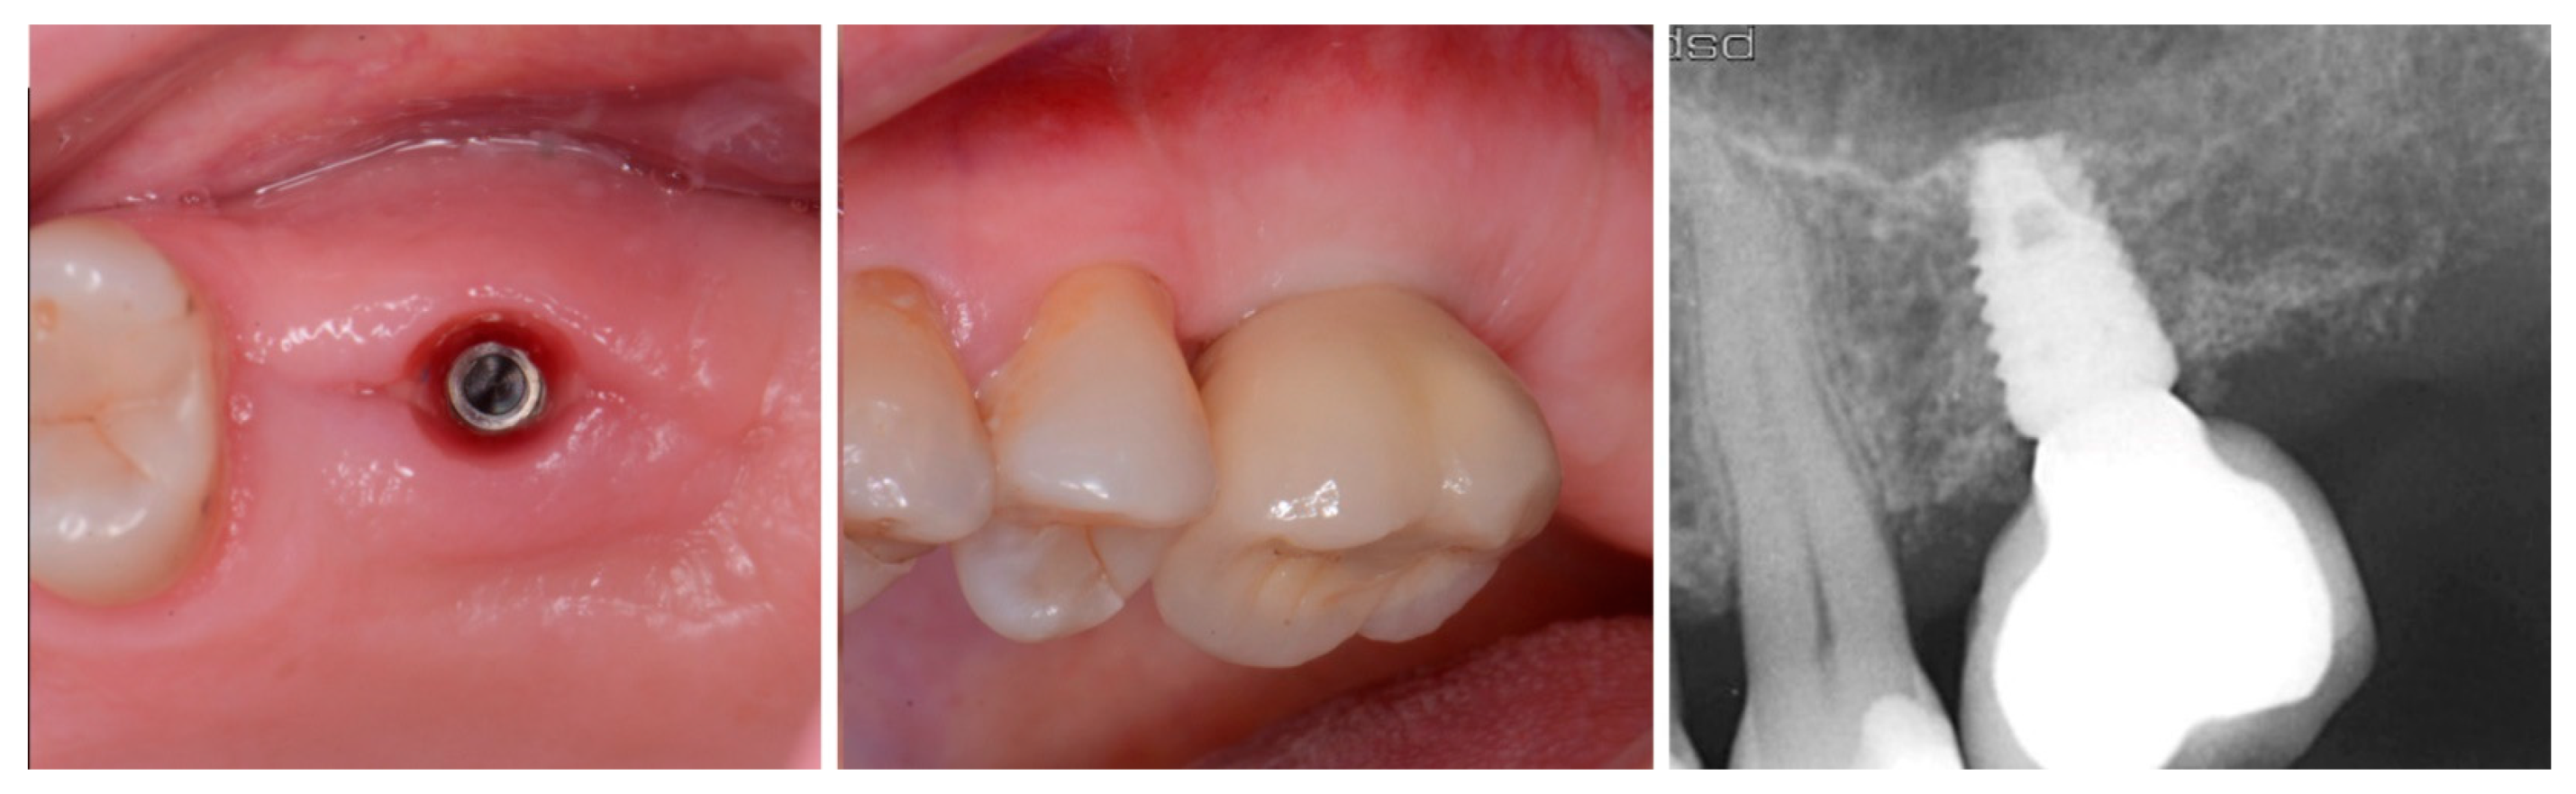

Figure 6.

Exposure of the integrated implant after 10 weeks of healing (left). Screw-retained restoration placement (middle) and a radiograph to document seating of the restoration at the implant connector demonstrating conversion of the graft material to host bone (right).

A radiograph obtained at the 2-year recall demonstrated stability of the graft surrounding the implant (Figure 7). The implant and restoration remain in function with no issues reported by the patient or noted at routine recall appointments during the prior period since completion of the restoration.

Figure 7.

Radiograph at 2 years post-restoration placement demonstrating stability and maintenance of the grafted area.